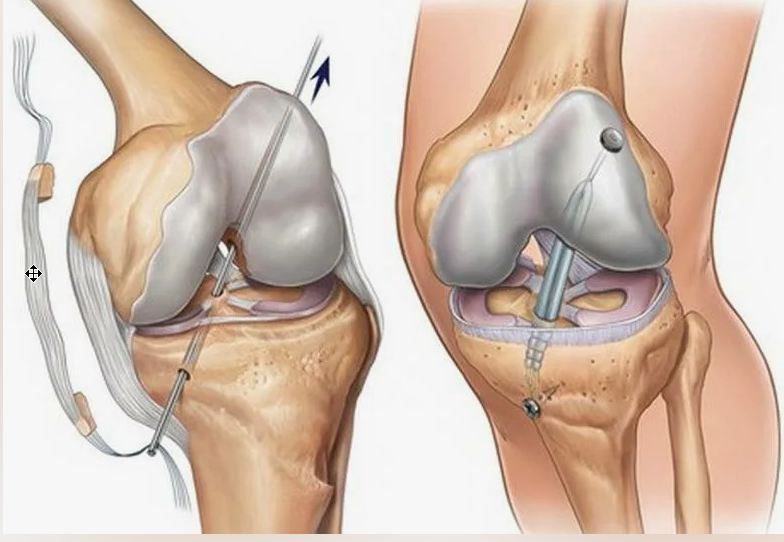

Заболевания и медицинские снимки: Жидкость в коленной чашечке